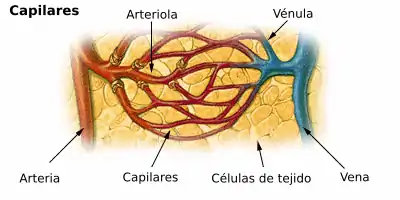

Las estructuras que conforman la microvasculatura son:

- las arteriolas,

- los capilares y

- las vénulas.

1.Arteriola

La arteriola posee en su pared una capa muscular, que al contraerse aumenta la resistencia vascular y disminuye el flujo de sangre.

2.Capilar

- Un capilar sanguíneo es un vaso de diámetro entre 8 y 12 µm. Su pared está formada por una sola capa de células endoteliales y recibe pasivamente el flujo vascular que le llega.

3.Vénula

- Una vénula es un vaso con un diámetro entre 15 y 100 µm. Su pared no tiene fibras elásticas ni células de músculo liso y se dilatan fácilmente.